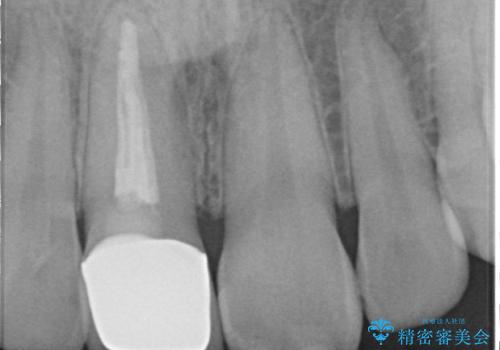

- 前歯の見た目の改善を求めて来院されました。

ジルコニアクラウンによる審美性の改善を計画します。

失活歯のため捻転を改善し、根管治療は特に希望されなかったのでそのままとしました。

今回失活歯であったため捻転を取り反対側の前歯に揃えて補綴を行うことができました。